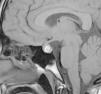

La paciente es remitida a endocrinología pediátrica tras el hallazgo de una cifra elevada de prolactina (198ng/ml, rango de normalidad: 8,5-26,5ng/ml). A la entrevista dirigida, la paciente refiere un año de visión borrosa intermitente y cefalea frontal de 3 meses de duración, acompañado de galactorrea unilateral de escasa cuantía. A la exploración física: talla 169,5cm (DE:+1,1), peso 53,3kg, IMC 19,29kg/m2 (DE:−0,79). Estadio puberal V de Tanner y fenotipo armónico. Ausencia de galactorrea, hirsutismo o acné. El hemograma y la bioquímica general fueron normales, destacando la determinación de prolactina (205,6ng/ml). La resonancia magnética (RM) (fig. 1) evidenció una glándula hipofisaria aumentada de tamaño, con borde superior convexo hacia línea media y aumento de señal sugestivo de cambios hemorrágicos subagudos. La glándula hipofisaria, impronta y oblitera la cisterna supraselar con efecto masa sobre el quiasma óptico. En el estudio oftalmológico se constató una hipermetropía leve, con normalidad en la campimetría y en el fondo de ojo. Con los datos obtenidos se estableció el diagnóstico de prolactinoma con apoplejía subclínica, iniciando tratamiento con cabergolina a dosis de 0,25mg la primera semana y 0,50mg/semana de mantenimiento. Al mes de iniciar el tratamiento, se aprecia en la RM de control (fig. 2), el adenoma con unas medidas de 10×8mm, probablemente sobreestimadas por los signos de sangrado, con una cifra de prolactina de 12,6ng/ml. En la actualidad la paciente presenta ciclos menstruales regulares, visión normal sin cefalea y ausencia de galactorrea.